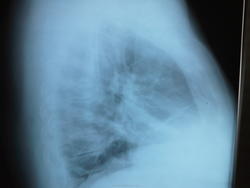

Женщина, 1950 г.р. Жалобы на боли в правой и левой половине грудной клетки. Соэ 52,лейкоциты 7.2, тромбоциты 343 з( норма до 320), HG 155( норма 140). Собственно по анамнезу все.Больше никаких сведений нет.

Возможно, очаговая пневмония вS8 справа.Справа  в средней доле линейная тяжистоть (дисковидные ателектазы, фиброз?). Хотелось бы и левую боковую.

Лейкоциты в норме, темп. Нет. Может это поствоспалительные изменения  нижней и средней долей с  плеврофиброзом. Но не пойму, что за полукруглая кольцевидная тень  в проекции 3 межребеья в прямой проекции и над диафрагмой ближе к заднему скату, на боковой?

Кольцевидная тень, скорее всего - наслоения легочного рисунка. Согласен с дисковидными ателектазами. Они, вместе с усилением легочного рисунка, побуждают предположить диффузное заболевание соединительной ткани: СКВ, дерматомиозит, склеродермию, ревматоидный полиартрит. При СКВ характерный симптом - высокое стояние диафрагмы.

Обычные дисковидные ателектазы.

Дисковидный ателектаз да. Наложение лег. рисунка в 2-х проекциях?! (Это я про кольцевидную тень,особенно в боковой проекции). Направлена на КТ.Когда вернется, доложу...Спасибо за комментарии.